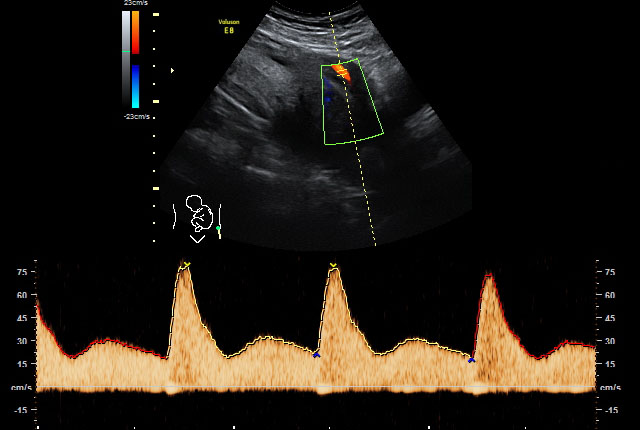

Wenn der Verdacht auf fetale Wachstumsstörungen und/oder fetale Fehlbildungen besteht, wird die Versorgungssituation des Ungeborenen durch eine spezielle dopplersonografische Untersuchung überwacht und die Funktion der Plazenta überprüft. Wir setzen hierbei den hochauflösenden Farbdoppler, also die sogenannte farbkodierte Doppler-Sonografie ein.

Bei der farbkodierten Doppler-Sonografie, einer bestimmten Form der Ultraschalluntersuchung, wird die Richtung des Blutflusses farblich dargestellt, um den Blutfluss in Arterien von dem in Venen unterscheiden zu können. Damit können auch Aussagen über das Ausmaß eventuell vorhandener Durchblutungsstörungen getroffen werden.